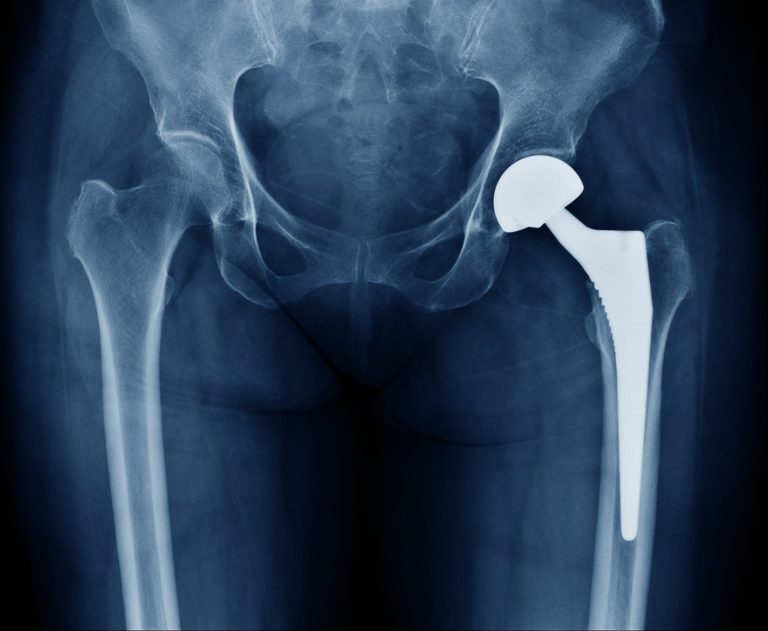

背景:对于初次全髋关节置换术(THA)采用基于前方的手术入路的好处,目前仍缺乏共识。本研究的目的是评估基于社区的卫生保健组织在初次髋关节置换中使用的各种入路在无菌性松动、感染和脱位方面的风险。

问题/目的:(1)在大型社区卫生保健组织中,初次全髋关节置换术的无菌性松动翻修、感染性翻修和脱位的发生率是多少?(2) 无菌性松动、假体周围感染和脱位的风险是否因THA手术入路而不同?

结论:直接前方入路、前外侧入路的优点是脱位风险较低,而且不增加早期翻修率。